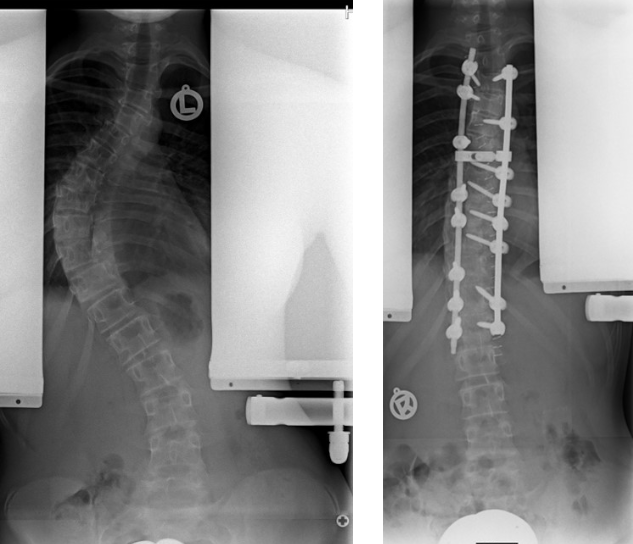

Wachstumslenkung (Vertebral Body Tethering - VBT)

Bei der VBT Methode, auch auch Anterior tethering genannt wird, wird operativ von vorne-seitlich an der Wirbelsäule ein sehr festes Band angebracht. Es soll das Wachstum auf der Konvexseite gebremst werden, damit die kürzere konkave Seite nachwachsen kann. Die Korrektur erfolgt also nicht bei der Operation, sondern erst allmählich während des Wachstums.

Gedacht ist es für Patientinnen und Patienten mir sehr flexibler Krümmung, die jedoch schon so weit fortgeschritten ist, dass man davon ausgeht, dass eine Korsettbehandlung allein nicht zum Erfolgt führt. Da noch eine Restbeweglichkeit erhalten bleibt, wird es auch als "Begradigung ohne Versteifung" propagiert und zunehmend auch bei ausgewachsenen Patientinnen und Patienten eingesetzt. Für diese ist es aber eigentlich nicht vorgesehen.

VBT-Methode

Aktuell wird es empfohlen für Krümmungen zwischen 35 und 70 Grad, die sich spontan um 50 Prozent und mindestens unter 30 Grad korrigieren lassen. Der optimale Zeitpunkt ist zu Beginn der Pubertät, wenn noch genügend Wachstumspotential vorhanden ist. Um dies zu bestimmen, sollte die Hand geröntgt werden. Setzt man das System zu spät ein und korrigiert vornehmlich nur über die Seile, dann ist die Gefahr groß, dass diese reißen. Setzt man das System zu früh ein, besteht die Gefahr der Überkorrektur, weil das Restwachstum schwer vorhersehbar ist.

Wie lange das funktioniert, ob die Wirbelsäule dann irgendwann doch versteift oder das Band ausreißt und wie es dann weitergeht, ist noch nicht abschließend geklärt, weil es keine Studien gibt, die die Patienten länger als fünf Jahre beobachtet haben. Für einige Patienten, die kurz vor Beginn oder am Anfang der Pubertät schon eine starke Krümmung haben, könnte dieses System durchaus auch dauerhaft von Vorteil sein. Es sollte jedoch nicht grundsätzlich als Ersatz für eine Korsettbehandlung gesehen werden.